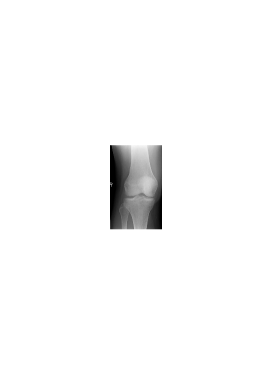

We illustrate now the suitability of the proposed mixed dictionary to produce high quality approximations of the set of X-ray medical images shown in Fig. 3. This set of twenty images is the Lukas 2D 8 bit medical image corpus, available on [33].

Image PSNR DWT DCT OMP2D HBW Hand1 48.1 30.0 26.4 39.0 72.6 Foot1 48.6 26.6 26.1 30.4 44.9 Foot0 48.6 25.5 26.1 42.7 65.2 Head0 47.4 25.3 24.3 51.9 63.2 Knee1 48.0 22.7 23.0 34.5 59.8 Sinus0 47.1 18.9 18.7 31.3 46.7 Hand0 48.8 18.6 18.7 32.2 47.9 Head1 46.4 17.5 15.1 38.3 44.4 Knee0 49.1 17.4 17.5 33.2 45.9 Sinus1 45.8 17.2 17.1 29.5 43.0 Breast0 44.3 15.7 15.3 36.7 41.0 Breast1 44.3 11.5 11.2 27.7 29.7 Thorax0 44.1 10.6 10.9 25.1 27.4 Thorax1 43.4 10.3 9.6 25.4 26.3 Leg0 48.9 8.2 8.4 21.2 22.3 Leg1 49.2 5.8 5.9 15.1 15.4 Pelvis1 44.3 4.8 4.7 12.3 12.6 Pelvis0 44.4 4.6 4.7 12.4 12.6 Spine1 47.0 3.5 3.6 9.3 9.4 Spine0 47.4 2.9 2.8 7.1 7.7